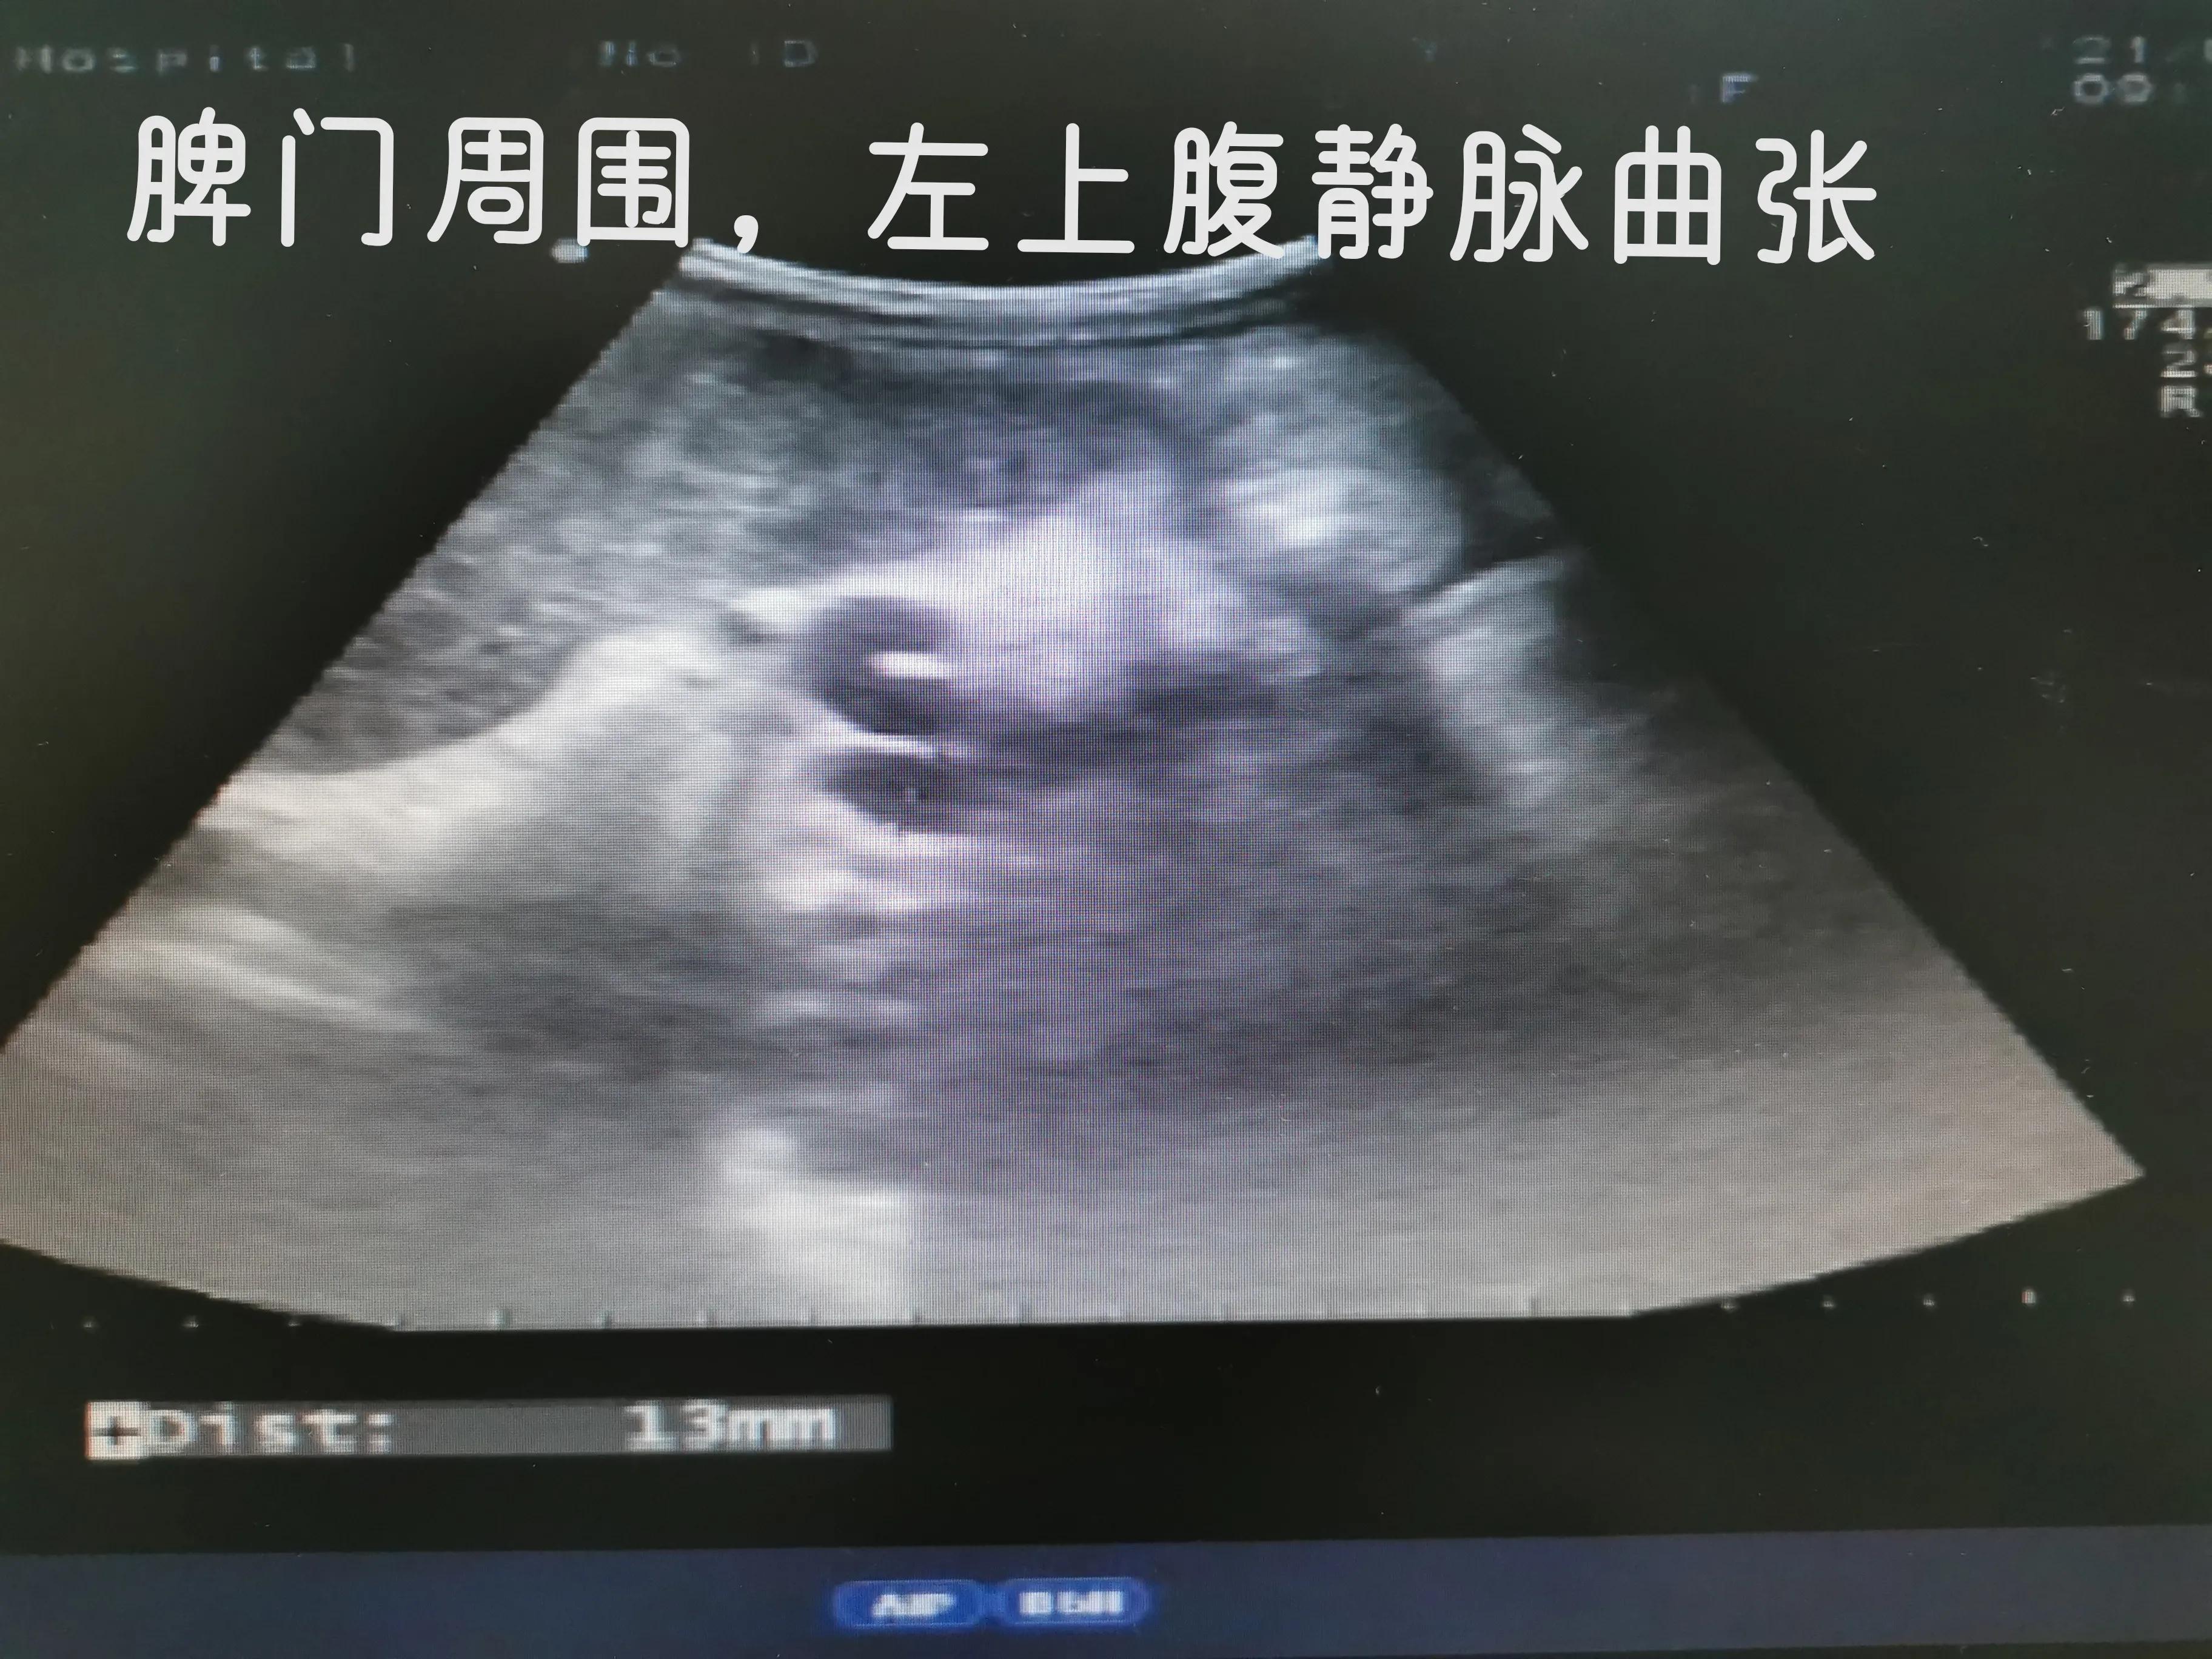

下面我们看看肝硬化失代偿期并肝癌病人肚子里面的情况

食管胃底静脉曲张-造成吐血的原因